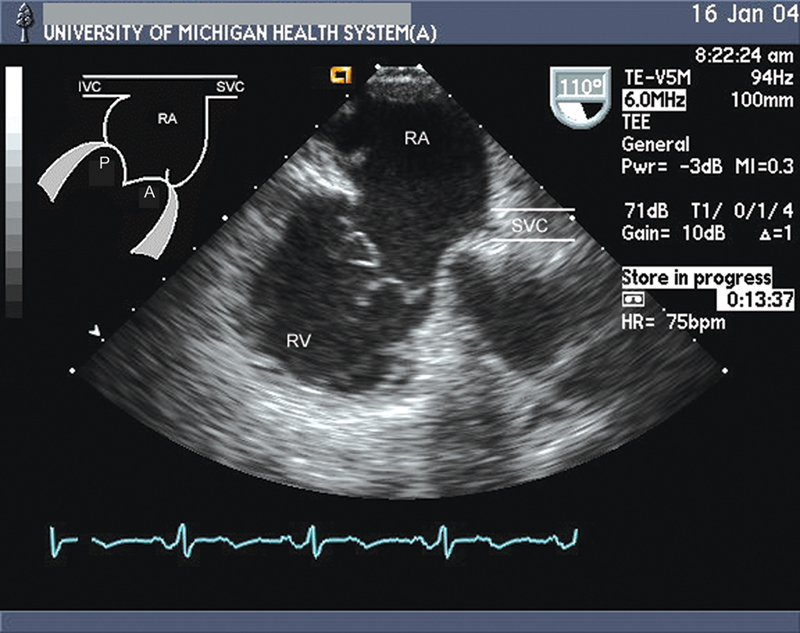

فحوصات تشخيصية لبعض امراض القلب والشرايين التاجية